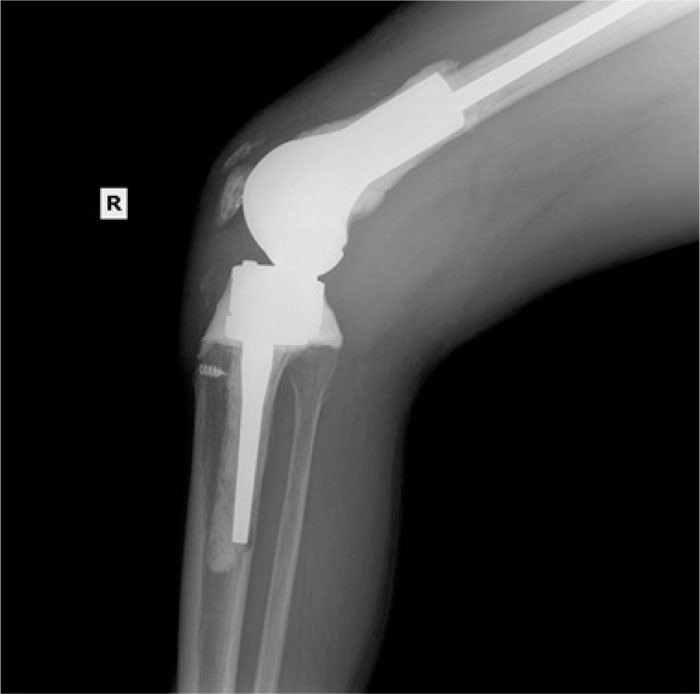

A Comparison of Clinical After Total Knee Arthroplasty in Nickel Allergy In Joint Replacement Metal allergy in knee arthroplasty patients is a controversial topic. Different metal ions may induce diverse allergic symptoms, for example: We aimed to conduct a scoping review to clarify the management of. Mh is a type iv hs. However, if patients develop metal allergy following their primary tka, the evidence presented supports revision surgery with hypoallergenic components with satisfactory. The. Nickel Allergy In Joint Replacement.

A Comparison of Clinical After Total Knee Arthroplasty in Nickel Allergy In Joint Replacement Metal allergy in knee arthroplasty patients is a controversial topic. Mh is a type iv hs. Nickel ions may create implant loosening, and release. Orthopaedic implants contain nickel because of its ability to provide increased strength and durability. However, if patients develop metal allergy following their primary tka, the evidence presented supports revision surgery with hypoallergenic components with satisfactory. We. Nickel Allergy In Joint Replacement.

From www.arthroplastyjournal.org